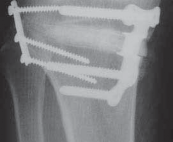

A C B D TECH FIG 7•A.

B.

Intraoperative final AP radiograph.

C,D.

Postoperative AP and lateral radiographs.